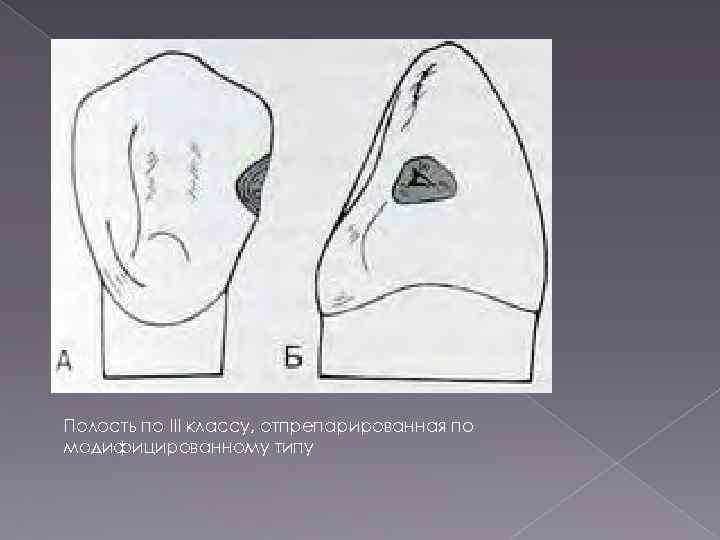

Препарирование кариозных полостей III класса: пошаговое руководство с фото